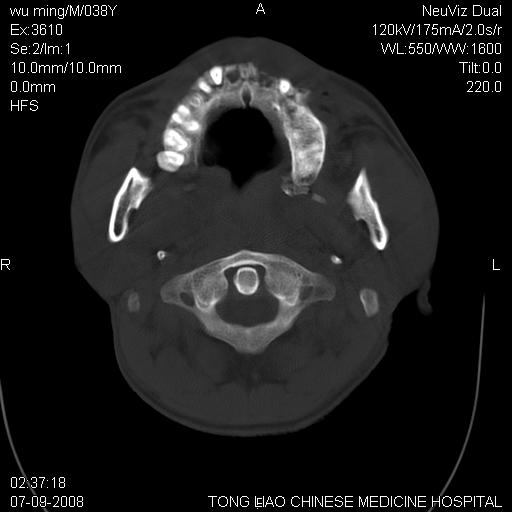

标题: CT14544:患者5楼坠下15分钟后CT扫描,2小时后死亡,请战友指 [打印本页]

标题: CT14544:患者5楼坠下15分钟后CT扫描,2小时后死亡,请战友指

颅底多发骨折。

颅底多发骨折.

颅底多发骨折.上颌骨多发骨折

右侧眼眶,上颌骨,鼻骨、上颌窦等很多

考虑:面骨、颅底骨多发骨折,颅内高压(脑肿胀)。

面骨、颅底骨多发骨折,右侧硬膜下小血肿,弥漫轴索损伤,死亡原因可能是多种因素致。

1)颅底骨及颌面骨多发性骨折。2)副鼻窦及双侧鼻腔积血。

颅底骨折,窦腔内积血。考虑死亡原因为脑水肿压迫脑干或因大量失血死亡。

前颅窝颅底骨折,死的原因应该从头部来看不用说就是重度颅脑损伤。

颅底、上颌骨,双侧颧骨多发骨折。死因或许与此无关,是否有腹部脏器损伤有关

考虑:面骨、颅底骨多发骨折。从五楼摔下还伤着头了,不死才怪;估计有弥漫性轴索损伤。